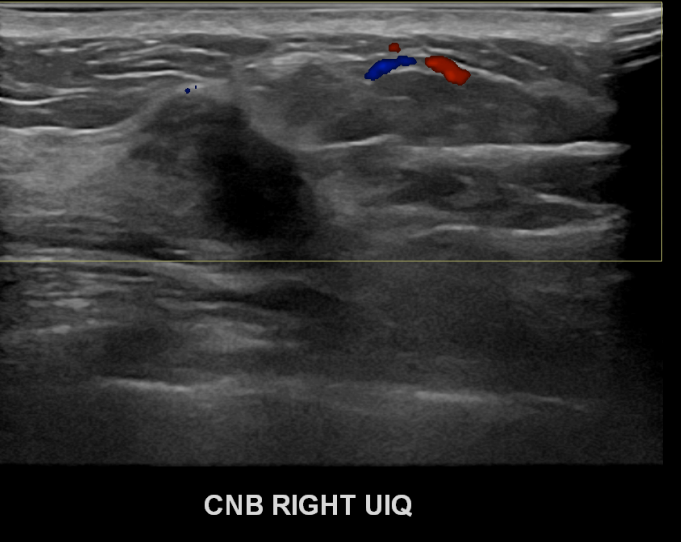

아산유외과개원후 690번째 유방암진단

상기환자 우측유방에멍울이만져져 내원하신 50대여성분으로 우측유방의 혹 조직검사시행후 유방암 진단되었습니다